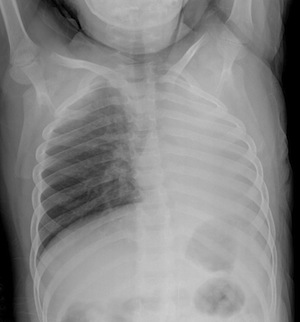

Boy With Worsening Respiratory Function: A Case History Figure 1 – The chest film shows opacification of the left lung.

Figure 2 – Complete opacification of the left lung is evident after 24 hours of therapy.

Figure 3 – Near complete aeration of the left lung is apparent after the foreign body was removed.